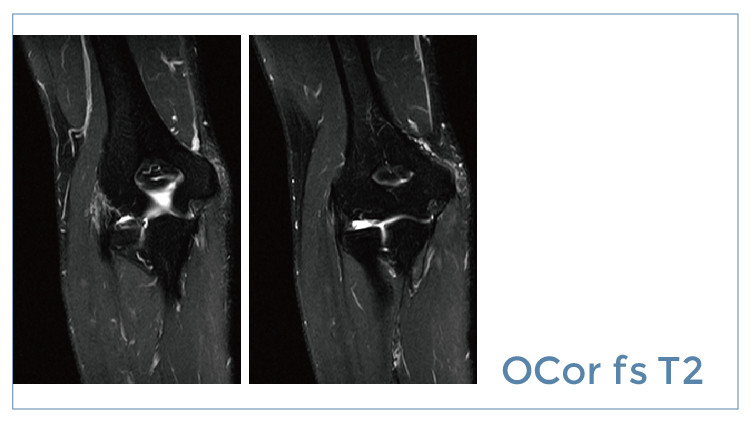

【朗润影像档案】20190712磁共振影像病例结果讨论

【朗润影像档案】磁共振影像病例分享(编号20190712)